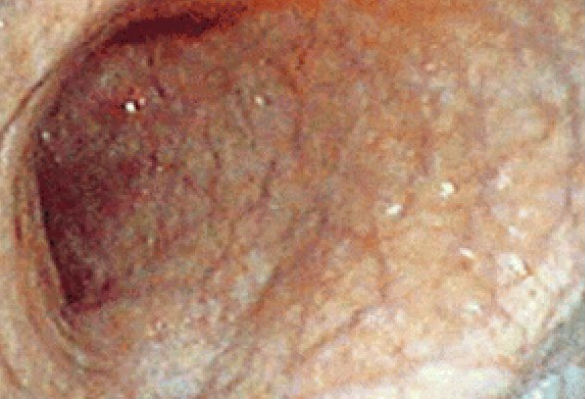

Следует сказать, что УЗИ, рентгенография, КТ брюшной полости без контрастных веществ, МРТ не дают исчерпывающей информации о патологии. Наибольшую диагностическую ценность представляет методы эндоскопии, гастроскопии и её разновидности, например, хромогастроскопия. Это метод исследования стенок желудка после предварительной окраски их поверхности.

С помощью гастроскопа наблюдают истончение и сглаженность стенок. Хорошо просматриваются сосуды желудочных стенок (в норме они не видны). Исследования биоптата стенок выявляет дистрофию и атрофию желез желудка. Ценным является метод внутрижелудочного измерения рН. Почти всегда выявляется изменение рН среды желудка в сторону нейтральной реакции, вплоть до ахилии. В перечень обязательных методов диагностики атрофического гастрита входит исследование микрофлоры желудка. Многие специалисты считают рутинное выявление бактерий Хеликобактер пилори малоинформативным диагностическим методом.